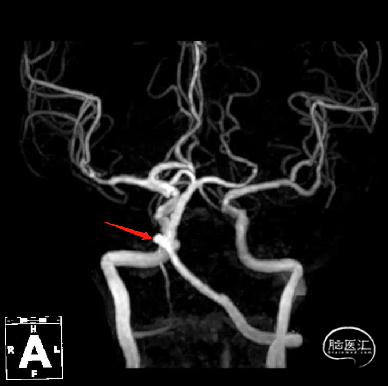

术前MRI+MRA示:脑桥急性梗死,动脉瘤位于基底动脉近端,左侧椎动脉优势。

通过3D工作位测量出基底动脉瘤瘤颈最宽处:6.5mm;载瘤动脉尺寸:近端直径3.7mm,远端直径4.2mm。

基底动脉不规则动脉瘤,瘤颈最宽处6.5mm。